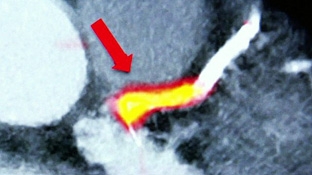

Có thể phát hiện nguy cơ đau tim bằng kỹ thuật chụp cắt lớp mới

- Cập nhật những tiến bộ mới trong phẫu thuật và can thiệp cấp cứu bệnh lý động mạch chủ